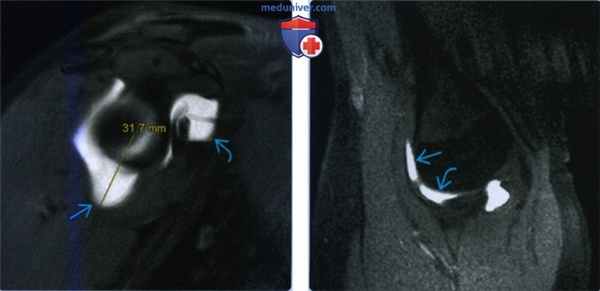

(Слева) На косой сагиттальной МР-артрограмме Т1ВИ FS y женщины 32 лет с разнонаправленной нестабильностью определяется растяжение нижней капсулы на 31,7 мм, превышающее норму в 24 мм. Кроме того, имеется сильное растяжение суставной капсулы около ротаторного интервала.

(Справа) На МР-артрограмме Т1ВИ FS с отведением и наружной ротацией у этого же пациента определяется симптом серпа с контрастом между передним пучком нижней суставно-плечевой связки и головкой плечевой кости. Кроме того, имеется симптом треугольника (треугольной пространство между нижней суставно-плечевой связкой, головкой плеча и суставной впадиной).в) Дифференциальная диагностика разнонаправленной нестабильности плечевого сустава: